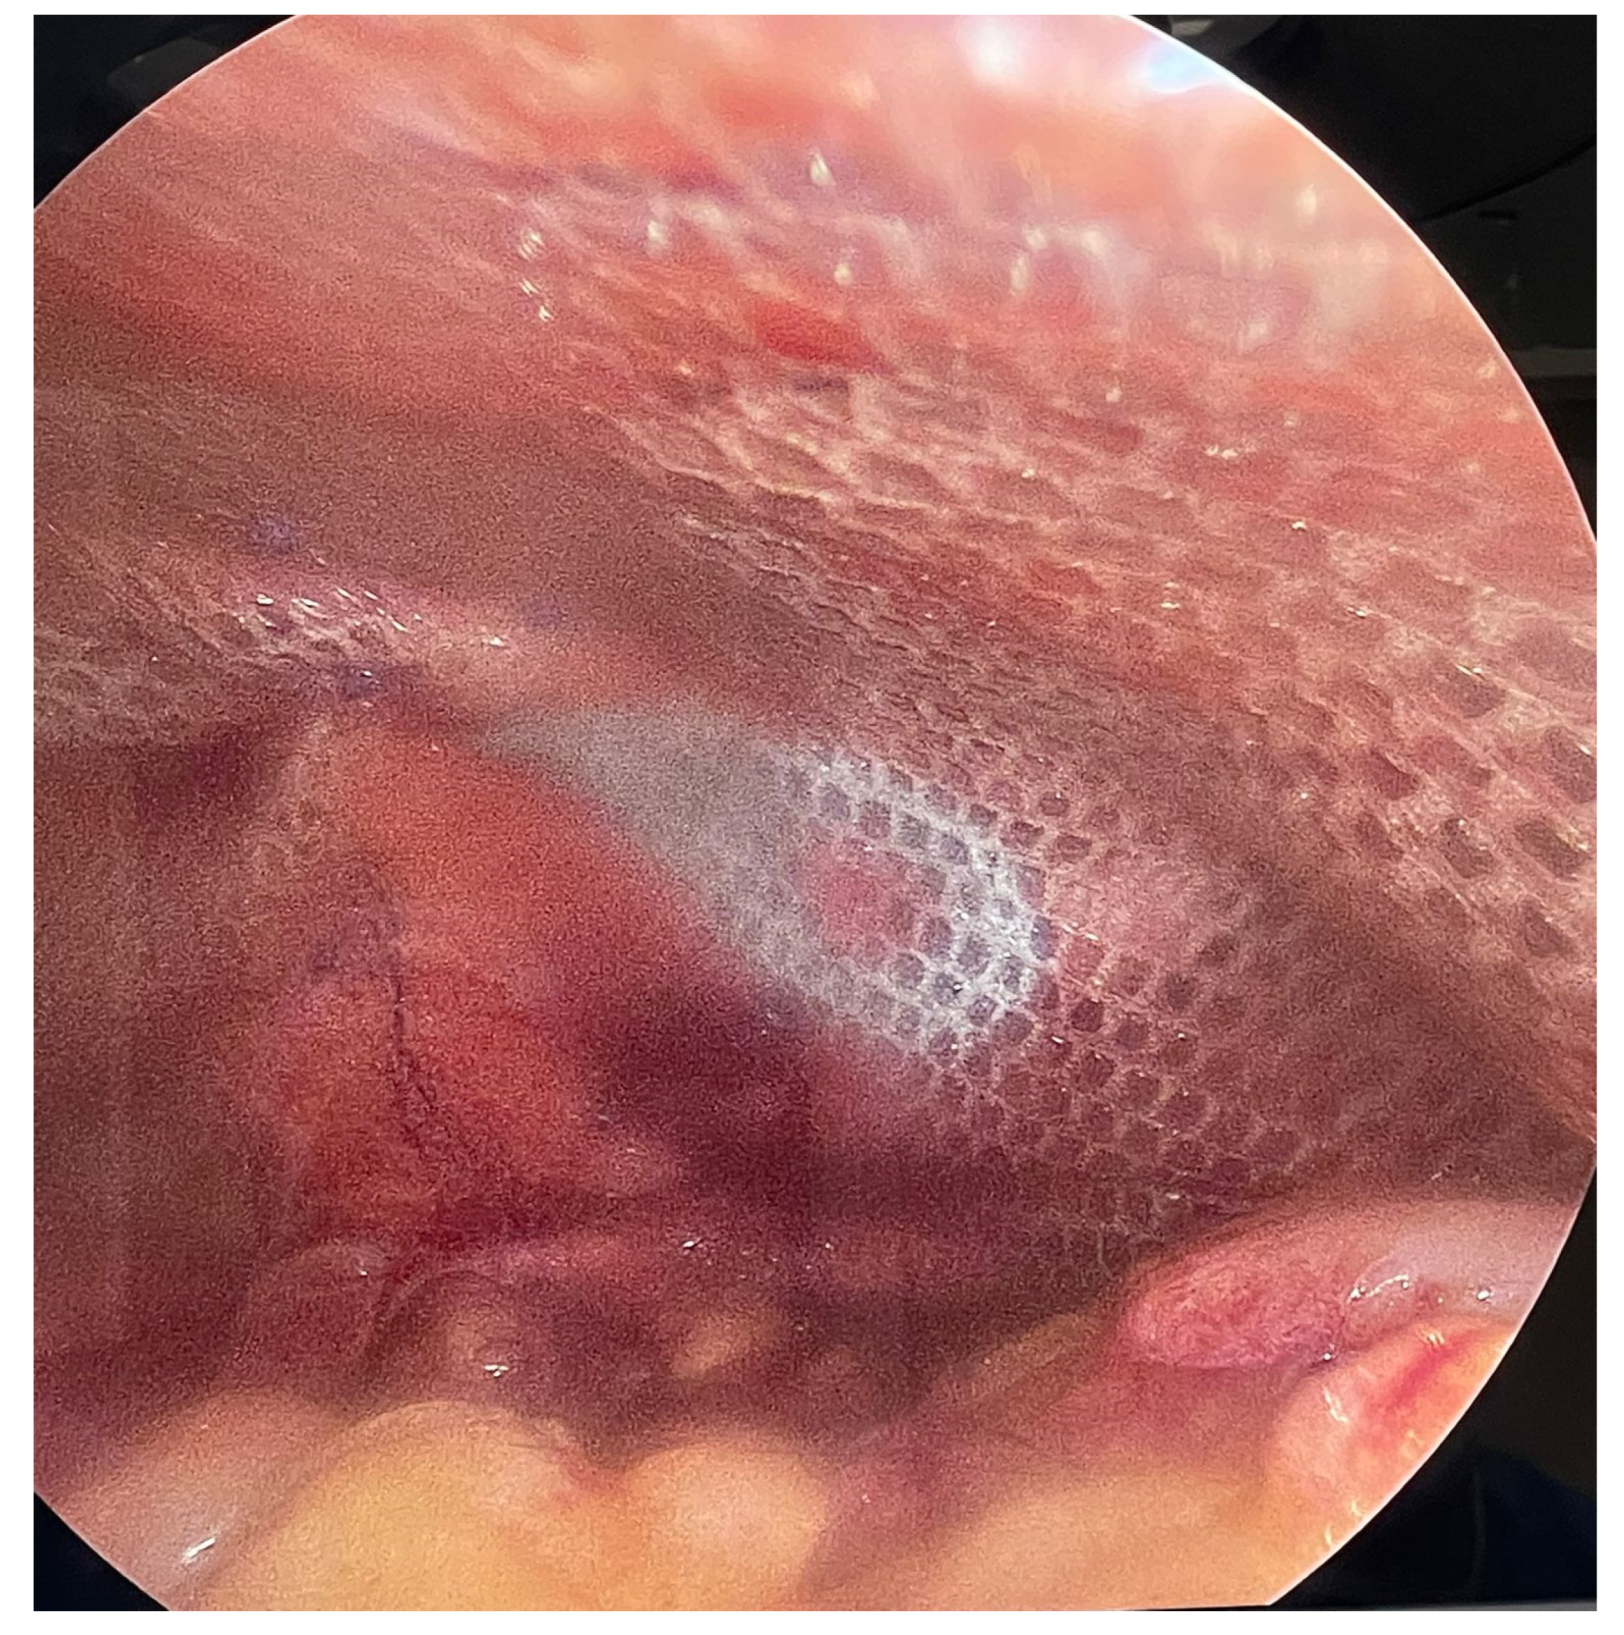

Figure 3.

Clinical photograph of the external appearance of the hernial sac with attenuated overlying skin.